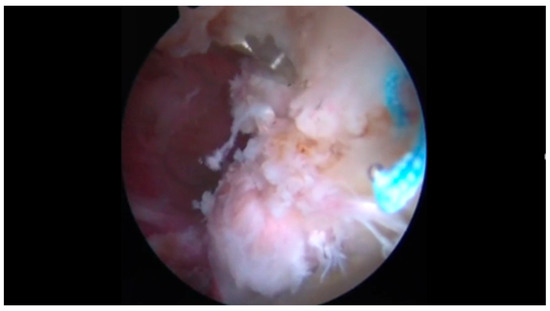

Tractionless Arthroscopic Treatment of Suspected Hip Septic Arthritis in Adults: A Single-Center Retrospective Case Series with Minimum One-Year Follow-Up

by Nadav Graif, Ran Atzmon, Aimee Steen, Shai Factor, Samuel Belmont, Michal Dekel, Ehud Rath and Eyal Amar

Background: Septic arthritis of the hip (SAH) requires emergent surgical intervention. While open arthrotomy has been the traditional approach, arthroscopic treatment is emerging as an effective alternative. Tractionless techniques in adult populations remain understudied. Methods: Twenty-one patients (22 hips) met inclusion criteria. Six [...] Read more.

Background: Septic arthritis of the hip (SAH) requires emergent surgical intervention. While open arthrotomy has been the traditional approach, arthroscopic treatment is emerging as an effective alternative. Tractionless techniques in adult populations remain understudied. Methods: Twenty-one patients (22 hips) met inclusion criteria. Six patients (7 hips) were excluded for age < 18 years, post-COVID osteomyelitis, prior hip surgery, or insufficient records, resulting in a final cohort of 15 patients. All fifteen patients underwent tractionless arthroscopic irrigation and debridement for suspected SAH (2014–2023). Inclusion required ≥2 clinical criteria (hip pain, limited range of motion, inability to bear weight, fever > 38 °C) AND ≥ 1 laboratory criterion (leukocytosis, elevated CRP, synovial WBC > 50,000, positive culture). Primary outcomes included Visual Analog Scale pain scores, inflammatory markers, and complications. Results: Median age was 33 years (range 20–76); 60% were female. VAS scores improved from 7 (6–10) to 1 (0–3) at discharge (p < 0.001). CRP levels decreased from 115 mg/L (35–206) to <5 mg/L (<5–9) postoperatively (p < 0.001). Positive cultures were obtained in 26.7% of cases, predominantly methicillin-sensitive Staphylococcus aureus. No perioperative complications occurred. Histopathological analysis revealed tenosynovial giant cell tumor (TGCT) in 33.3% of cases, representing an important differential diagnosis. Among non-TGCT cases, the culture-positive rate was 40%. No infection recurrence was observed during a minimum one-year follow-up. Conclusions: Tractionless arthroscopic irrigation and debridement appears effective for managing suspected SAH in adults, achieving significant improvements in pain scores and inflammatory markers without perioperative complications. This technique offers potential advantages by eliminating traction-related risks while maintaining effective joint debridement. Additionally, TGCT should be considered in the differential diagnosis of suspected SAH with culture-negative inflammatory arthropathy. Full article

Show Figures

Figure 1